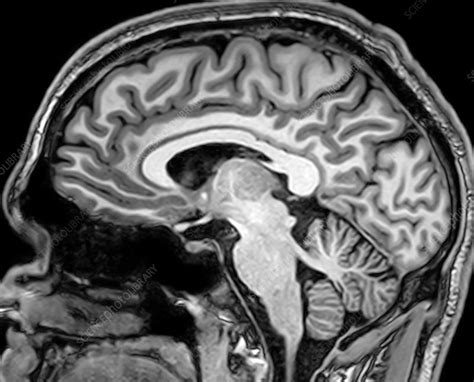

If you collect this light, using fancy mathemagics, you can plot relaxation time across the brain!

high spatial resolution: ~1 mm

this is measured using the receiver head coil

- high-resolution (1 mm)

- "anatomical scan"

- T1-weighted image

[x, y, z]